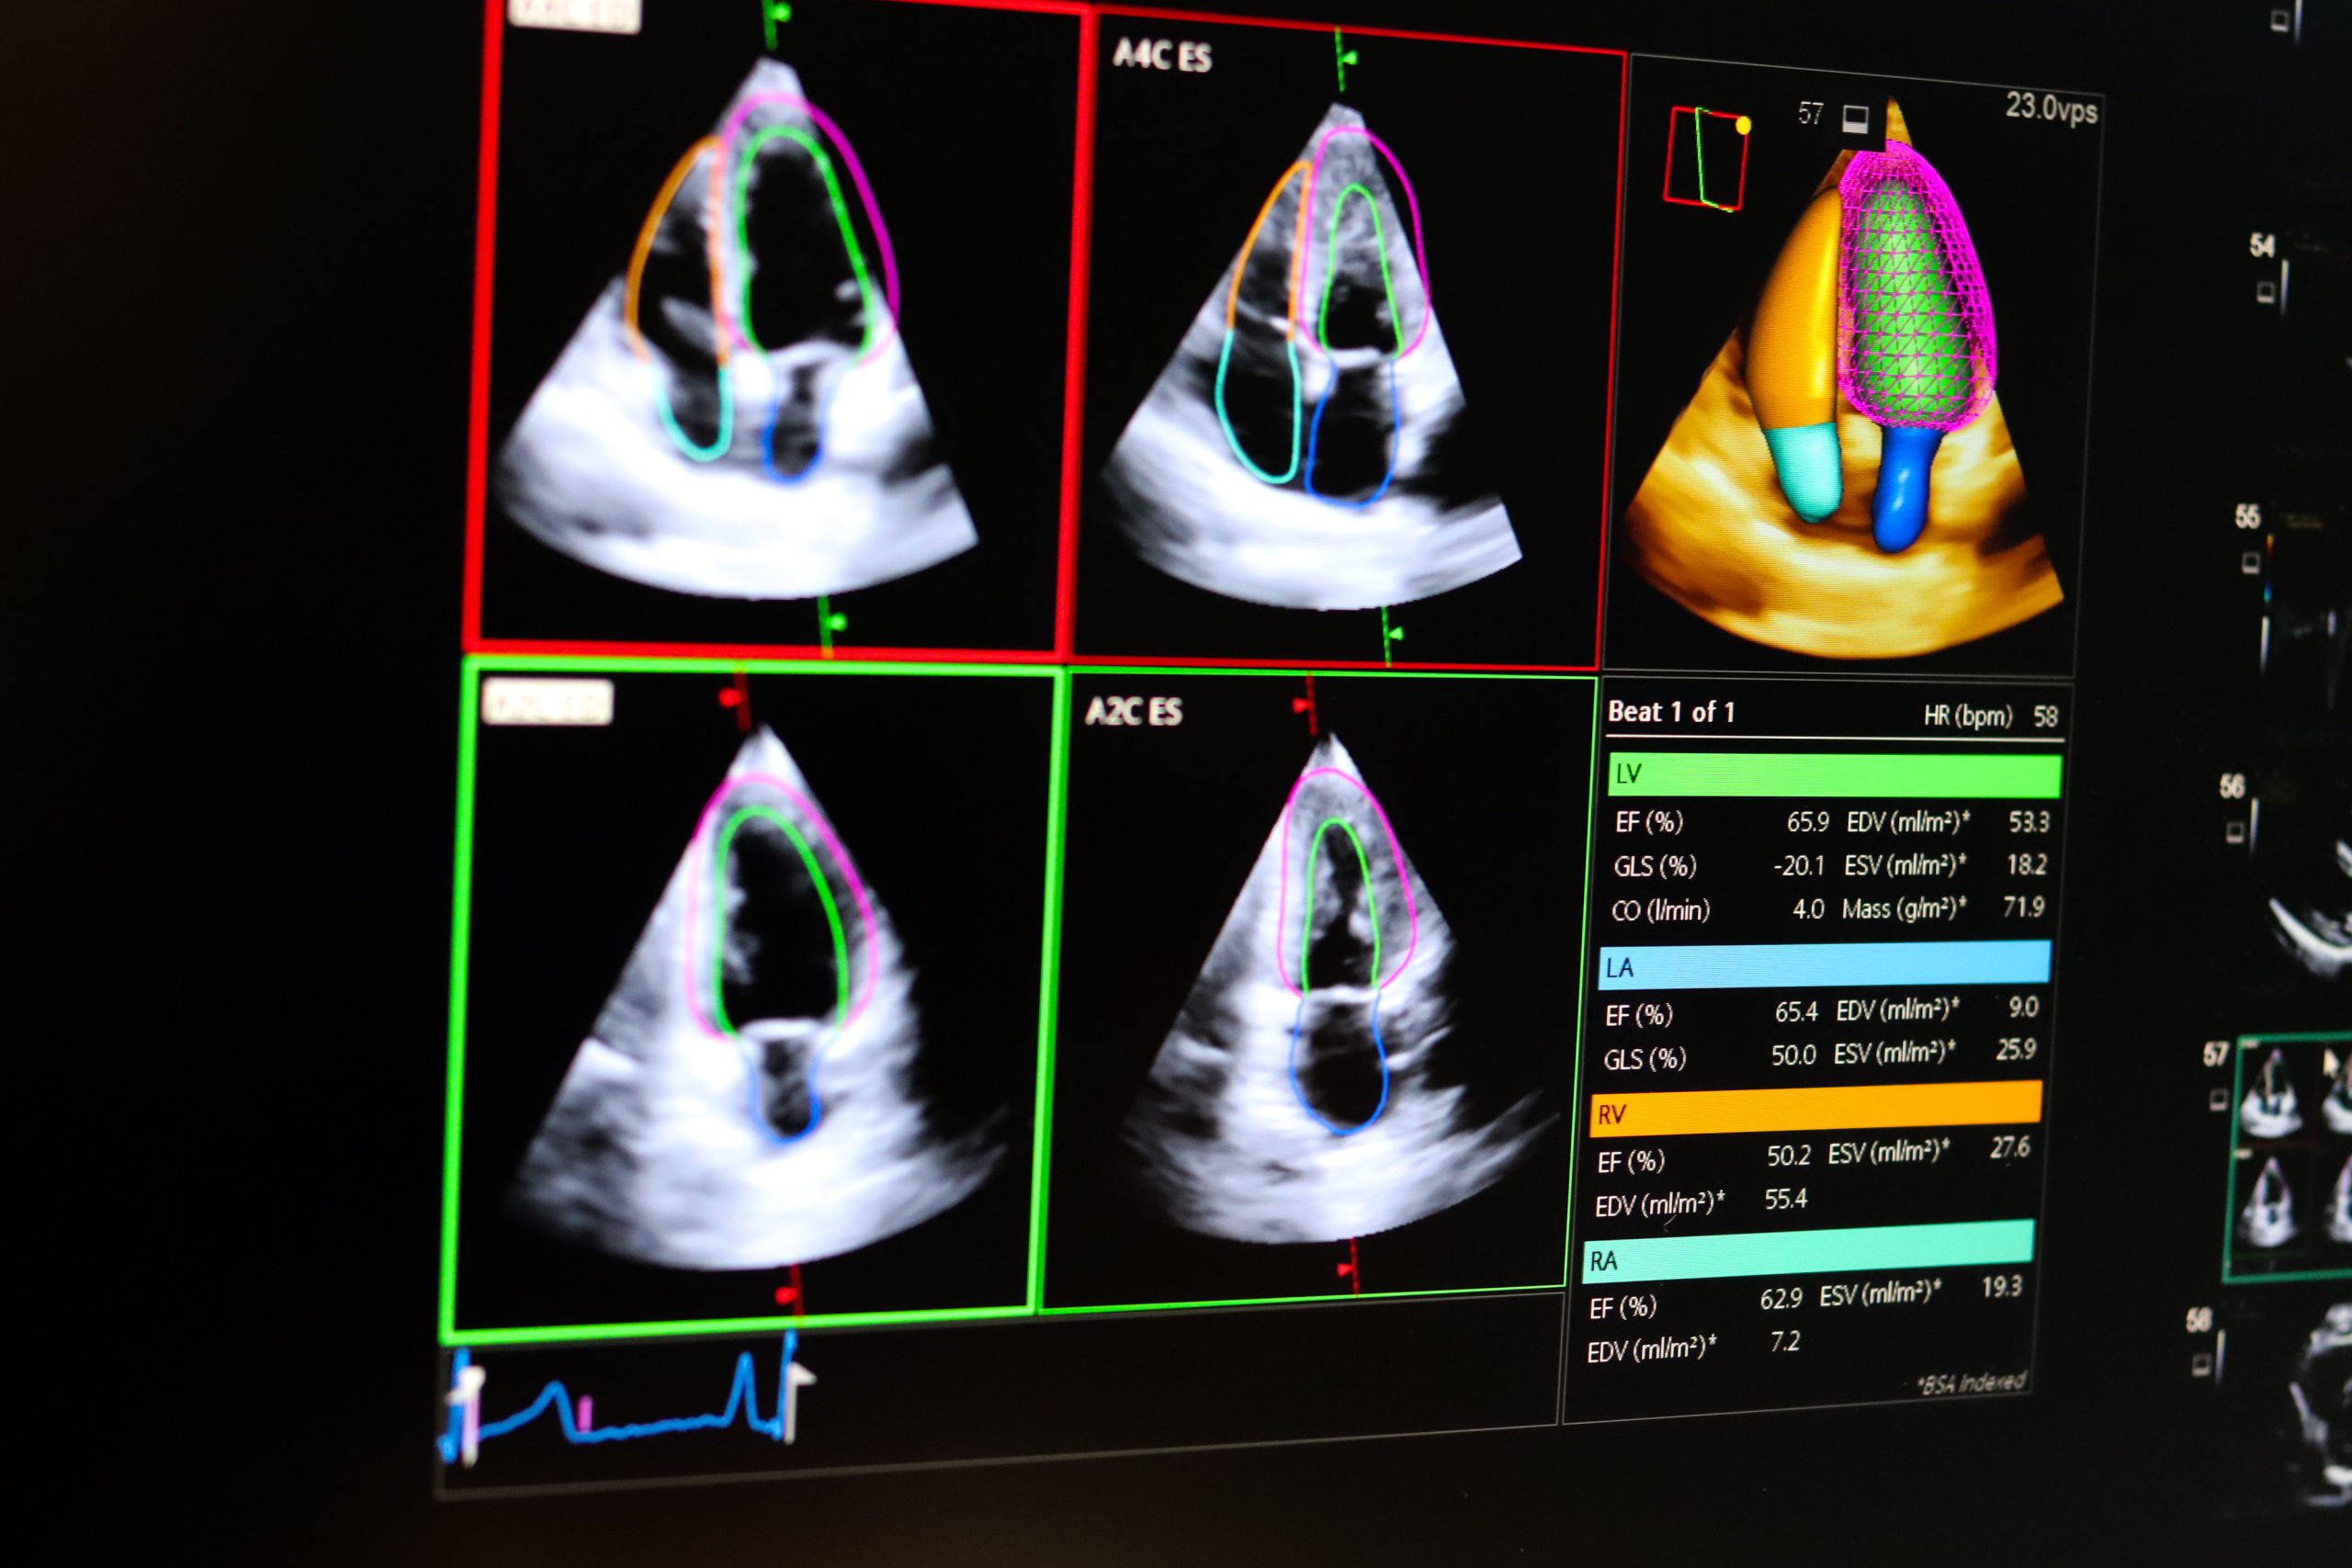

Automatické merania šetria čas a zvyšujú presnosť. V praxi to znamená, že po vyšetrení pacienta echokardiografický prístroj automaticky zrealizuje základné merania – najčastejšie rozmery a funkcie srdcových oddielov a prietoky chlopňovým aparátom. Tieto údaje urýchľujú vyšetrenie pacienta.

Na Echokardiografickom oddelení VÚSCH sa využíva aj trojrozmerná (3D) echokardiografia, ktorá posúva možnosti diagnostiky ešte ďalej. „Údaje získané touto metodikou dokáže artificiálna inteligencia tiež zhodnotiť. Okrem už celosvetovo rozšíreného 3D hodnotenia funkcie srdcových oddielov dokáže 3D AI vytvárať aj modely srdcových chlopní. Vďaka tomu lepšie rozumieme morfológii a mechanizmu ochorení,“ približuje lekár.

Ďalším cieľom vývoja je zdokonalenie softvéru na tvorbu 3D modelov srdcových chlopní, ktoré majú význam nielen v diagnostike, ale aj pri plánovaní kardiochirurgických a intervenčných zákrokov.

,,Neustále prebieha vývoj v zlepšení softvéru na vytváranie modelov chlopní, čo nás opäť posunie dopredu. Budeme teda mať, verím tomu, kvalitnejší obraz a lepšiu predstavu o chlopni a jej funkcii. Softvér dokáže hodnotiť jednotlivé parametre, či už dynamické alebo statické, ktoré sú dôležité pri kardiochirurgických záchovných výkonoch aj pri intervenčných výkonoch, ktoré sa realizujú transkatétrovo cez cievu,“ uzatvára Kurečko.